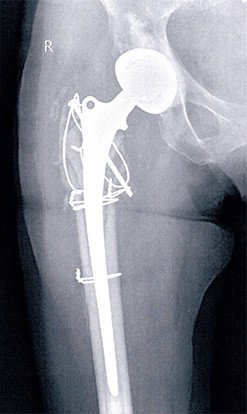

Oberschenkelbruch auf Prothesenhöhe

Die 77-jährige Patientin zog sich bei einem Sturz einen Bruch des Oberschenkels auf Prothesenhöhe zu.

Bei der Operation zeigte sich eine relativ starke Zertrümmerung des Knochens oberhalb des Bruches. Der Prothesenschaft selbst war durch diesen Bruch nicht mehr fest, sondern gelockert. Der Schaft musste entfernt und durch einen neuen ersetzt werden. Wir haben einen zementierten Schaft gewählt, der hier den Vorteil hat, dass die Trümmer sich besser an den Knochenzement anmodellieren lassen. Die diversen Fragmente wurden durch Schrauben und Drähte stabil fixiert. Während der Operation zeigte sich, dass die Hüfte instabil war, weshalb auch die Pfanne ausgewechselt wurde.

Der postoperative Verlauf war unauffällig, die Patientin hat sich gut vom Eingriff erholt. Aktuell ist sie beschwerdefrei und auch stockfrei gut gehfähig. Die Patientin ist mit dem Resultat zufrieden.